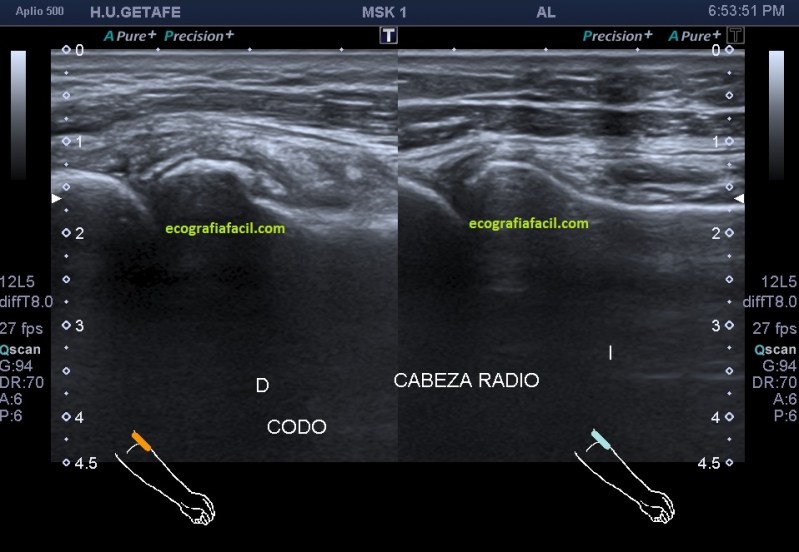

Me dirigí inmediatamente a la segunda fase de la exploración del protocolo de codo, que siempre es el epicódilo y aquí me encontré lo que al apostre sería la causa de los hallazgos que te describo en este post. Inmediatamente me llamó la atención los cambios en la superficie ósea de la cabeza del radio en el corte longitudinal de la región donde debo ver, cabeza de radio, articulación y epicóndilo, como ves en la imagen número 2.

La flecha amarilla señala un defecto de continuidad en la cortical ósea de la cabeza del radio, en forma de cueva. Ya sabía que aquí no había una epicondilitis, mejor dicho, no había solo una epicondilitis…

La imagen 9 es comparativa, para que veas normalidad y patología en una misma foto. No solo es normalidad de la cortical del hueso, la fractura modifica el tejido adyacente al foco, lo inflama y lo vuelve heterogéneo, afectando notablemente en este caso a la ecoarquitectura de la articulación globalmente.